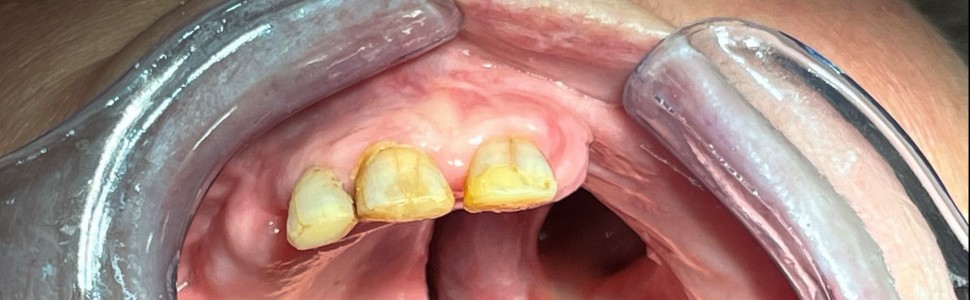

Rehabilitacja protetyczna pacjentów onkologicznych po zabiegach resekcyjnych w obrębie jamy ustnej. Część 1

Zabiegi chirurgiczne mające na celu leczenie nowotworów złośliwych okolicy szczękowo-twarzowej skutkują utratą znacznej ilości tkanek własnych pacjenta. W artykule opisano proces rehabilitacji protetycznej tej grupy pacjentów, omówiono poszczególne etapy postępowania i rodzaje najczęściej stosowanych obturatorów protetycznych.

Surgical procedures aimed at treating malignant neoplasms of the maxillofacial area result in the loss of a significant amount of the patient’s own tissues. The article presents the process of prosthetic rehabilitation for this group of patients, discusses the various stages of the procedure and the types of the most commonly used prosthetic obturators.